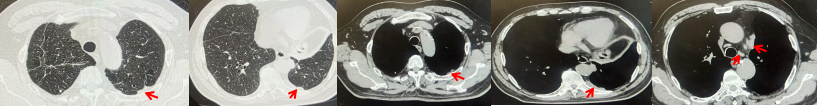

69岁男性,无糖尿病、高血压、心脏病等基础疾病,无吸烟、饮酒史,无肿瘤家族史。2023.06.07行胸部CT检查:右肺上叶胸膜下见肿物影,大小约33mm×22mm,边缘可见分叶,考虑恶性病变可能性大,双肺间质改变(如图1)。2023.06.14行“单孔胸腔镜下右肺上叶切除、肺门及纵隔淋巴结清扫、胸膜粘连松解术”;术后病理:(右肺上叶)腺癌(低分化,实体型占60%,不良腺体占40%),局灶伴神经内分泌标记表达(CD56、Syn),可见STAS及胸膜侵犯,未见确切神经侵犯及脉管内癌栓;(气管切缘)净;(淋巴结)未见转移癌0/26(2组0/2;4组0/6;7组0/2;对侧7组0/8;10组0/2;11组0/3;12组0/2;13组0/1)。术后分期pT2aN0M0 IB期,术后NGS基因检测:无驱动基因突变,PD-L1(22C3)TPS<1%。术后定期复查。

2024.11.19患者出现右侧胸痛,复查胸部CT检查示右侧胸膜肿物,大小约31mmX24mm,右侧4、5肋骨骨质破坏,考虑转移(如图2)。建议患者穿刺活检取病理明确诊断,患者拒绝,经MDT会诊后结合影像学表现及病史考虑为胸膜转移,肋骨转移,分期为rT0N0M1a IVA期,DFS仅仅17个月。2024.12.05起行信迪利单抗联合培美曲塞+卡铂方案治疗4周期,复查胸CT评效PR(如图3)。之后给予信迪利单抗+培美曲塞维持治疗6周期,期间复查CT评效PR(如图3)。目前信迪利单抗+培美曲塞维持治疗中,截止至目前PFS约为8个月,治疗期间未出现明显毒副反应。

图1:患者手术前(2023.06)胸部CT肺窗及纵隔窗

图2:患者胸膜及肋骨转移(2024.11)胸部CT肺窗、纵隔窗及骨窗

图3:患者免疫联合化疗治疗后胸部CT,(A、B)图展示信迪利单抗联合培美曲塞+卡铂治疗

4周期(2025.02)疗效,(C、D)图展示信迪利单抗+培美曲塞维持治疗6周期(2025.07)疗效